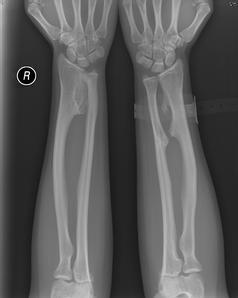

遗传性多发性骨软骨瘤也称为多发性外生骨疣、骨干端连续症、遗传性畸形性软骨发育异常症。典型发病部位是股骨、胫骨、腓骨的远近侧端及肱骨近侧端。临床表现为可触及的骨性肿块。本病无症状时无须处理,出现症状时,采取相应的治疗措施。